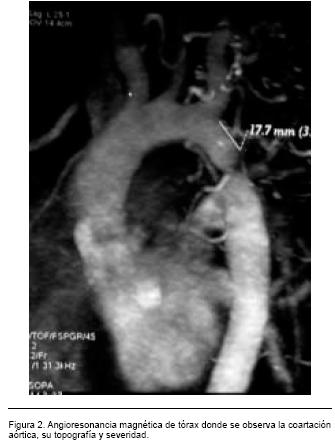

Como hecho destacable, durante el posprocedimiento presentó una crisis convulsiva de tipo gran mal. La tomografía computada de cráneo con contraste informó imágenes compatibles con dilataciones vasculares aneurismáticas, sin evidencias neuroimagenológicas de complicaciones agudas (Figura 3). Valorada en conjunto con neurocirujano y radiólogo intervencionista se plantea realización de una arteriografía de vasos con destino encefálico en la evolución (pendiente su realización). Clínicamente evolucionó con un excelente control de las cifras tensionales, sin necesidad de asociar drogas antihipertensivas. El control ecocardiográfico posprocedimiento informó la ausencia de gradiente residual significativo en aorta descendente.

Es frecuente su combinación con otras malformaciones intracardíacas tales como válvula aórtica bicúspide, comunicación interventricular, y anomalías a nivel de la válvula mitral; así como extracardíacas, dentro de las cuales se destacan los aneurismas intracraneanos a nivel del polígono de Willis, y la enfermedad poliquística hepatorrenal.(4) Constituye entre el 3 al 10% de las malformaciones cardíacas congénitas, siendo la 8ª malformación cardíaca por orden de frecuencia, y la 4ª causa de procedimientos de cardiología intervencionista y/o cirugía cardíaca durante el 1er. año de vida. Su prevalencia se estima en 2,09 por 10.000 nacidos vivos.3 Su incidencia es mayor en varones en relación 2:1 respecto al sexo femenino.(4) Desde el punto de vista fisiopatológico, la coartación de aorta determina una obstrucción al flujo sanguíneo de grado variable. Esto genera el desarrollo de HTA que afecta característicamente al hemicuerpo superior (sectorial), hipertrofia concéntrica del ventrículo izquierdo por sobrecarga sistólica del mismo, así como el desarrollo de circulación colateral que contribuye a mantener la perfusión del hemicuerpo inferior.(3) Clínicamente suele cursar de forma prácticamente asintomática hasta la 2ª a 3ª década de vida, momento en el cual aparecen las complicaciones atribuibles a la HTA. El diagnóstico debe sospecharse en aquellos pacientes jóvenes portadores de HTA que presenten diferencia de presiones entre los miembros superiores e inferiores, mayores a 30 mmHg.(4)

Librada a su evolución natural, el 90% de los pacientes fallece antes de los 50 años, siendo las principales causas de muerte la insuficiencia cardíaca izquierda (28%), la hemorragia cerebral por asociación con aneurismas en polígono de Willis (12%), disección aórtica (21%) y endocarditis infecciosa (18%).(3)